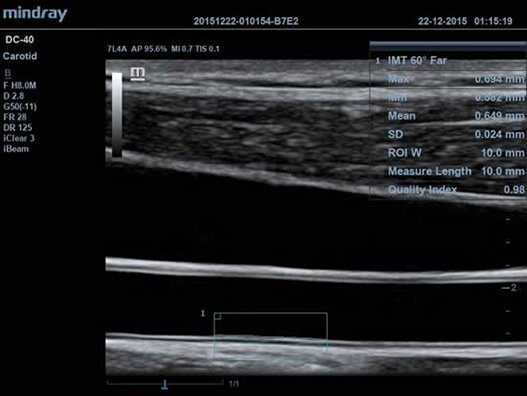

Клинические изображения

- Auto IMT Package – измерения и анализ толщины комплекса интимамедии (КИМ) сонной артерии;

- 7L4A Линейный датчик для поверхностных органов и структур, периферических сосудов, неонатологии и педиатрии

- Авто IMT (толщина интима-медиа) — автоматическое измерение толщины задней и передней стенок, дающее точные сведения о состоянии сонной артерии.